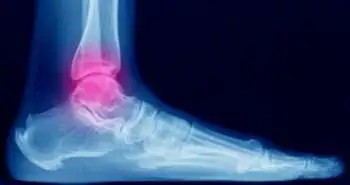

Transfibular Total Ankle Replacement is beneficial approach for pain management and improving functional outcomes in patients with ankle arthritis.

Trans fibular total ankle replacement shows remarkable improvements were observed in the range of motion, radiographic parameters and patient-reported outcomes for managing ankle arthritis, as per research published in Foot & Ankle International Journal. Ankle arthritis is a significant cause of disability and pain following degeneration of the quality of life. Prosthetic replacement of the ankle has shown to be a reliable choice with new advancements in surgical instrumentation and techniques as compared to arthrodesis with similar outcomes. This study aimed to assess the radiological and clinical outcomes of trans fibular total ankle replacement with two years follow-up.

A statistically significant improvement in the visual analog scale (VAS), Short Form-12 Physical and Mental Composite Scores, and American Orthopaedic Foot & Ankle Society (AOFAS) Ankle-Hind foot Score was seen after two years of follow-up  (P < .001). The ankle plantar flexion and dorsiflexion improved from 9.6 ± 5.8 and 6.2 ± 5.5 to 18.1 ± 7.6 and 24.2 ± 7.9, respectively. Management of neutral alignment of the ankle was also demonstrated at two years. No radiographic evidence of talar or tibial lucency was seen after the follow-up. Seven patients went through the operation again for symptomatic hardware removal; two patients noticed delayed wound healing. First patients operated with plate removal and flap coverage; whereas the second patient went for fibular plate removal. Postoperative prosthetic infection was seen in one patient who required operative debridement, placement of an antibiotic spacer, and removal of implants. Additional investigation is needed to discover the mid- and long-term performance of these implants.